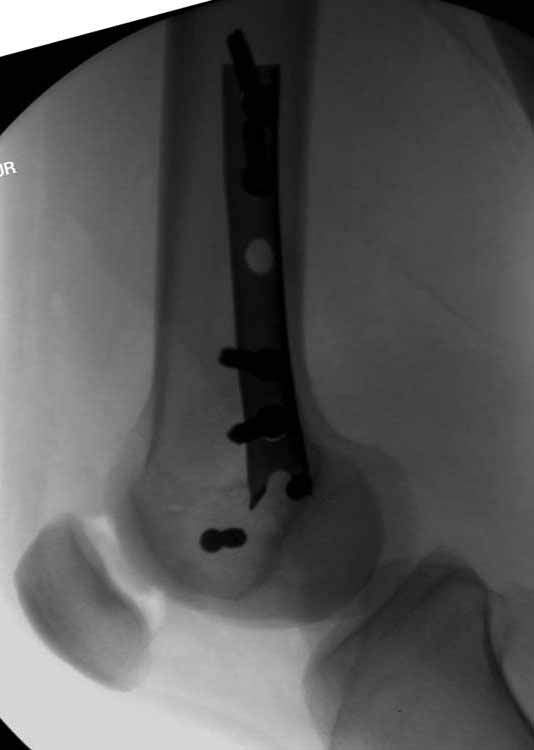

У больных как в этом случае, с вовлечением двух мыщелков правильно, что сделали вытяжение до операции. Здесь имеется флексионный компонент на другой стороне, и я бы рекомендовал операцию делать из двух доступов. Сперва фиксировать медиальную колонну custom made пластиной, обычно 1/3 тубулярной пластиной в 4.5 мм, потому что пока производители опаздывают с медиальной пластиной.

Пластину надо устанавливать на апексе перелома, иначе фрагмент начнет сползать. А на второй стороне, если имеется большой одиночный фрагмент тогда проблем не бывает, и их можно собрать компрессирующими винтами. Проблема наступает тогда когда многофрагментраность на латеральной стороне, где надо применить комбинированный метод, иногда несколькими пластинами. Или сменой позиции установки пластины, чтобы максимально прикрыть перелом и создать боковую поддержку.

Здесь пример медиальной пластины и латеральный комбинированный метод (у второго больного старый перелом тибиал плато, леченный где то и когда то)